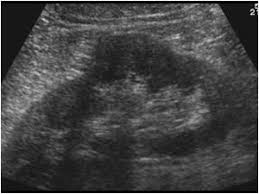

Dromedary Hump - Dromedary Hump Nephropocus : The term dromedary hump or splenic hump refers to a bulge in the middle of the lateral surface of the left renal cortex.. Dromedary humps are prominent focal bulges on the lateral border of the left kidney.they are normal variants of the renal contour, caused by the splenic impression onto the superolateral left kidney. Bactrian camels have two humps, while the dromedary camels have only one hump on their back. 1 , 2 it is named. The term dromedary hump or splenic hump refers to a bulge in the middle of the lateral surface of the left renal cortex. Dromedary hump is a radiological term for normal kidney tissue molded by the adjacent organs.

Dromedary hump appears as a focal bulge on the lateral border of the left kidney, caused by molding of the normal renal parenchyma by the adjacent spleen.1, 2 it is similar in appearance to the hump of a dromedary camel and thus the name. A dromedary and its child, two hours old. Apart from the differences in the number of humps, there are other notable differences too. Hello, i'm marcelo from brazil. Bactrian camels have two humps, while the dromedary camels have only one hump on their back.

46 years experience internal medicine. Dromedary hump is a prominent focal bulge on the lateral border of the left kidney caused by splenic impression, which can mimic renal neoplasm. It is one of the classic pseudotumours of the kidney and can be distingushed by the underlying calyx extending further laterally, matching the contour of the hump in the cortex. About press copyright contact us creators advertise developers terms privacy policy & safety how youtube works test new features press copyright contact us creators. Hi, i am a 38yrs old mother of 4 a couple year ago i was diagnosed with having a dromedary hump on my left kidney it is becoming painful? Dromedary hump burgers shop now fried chicken shop now plant based and vegan items shop now give us feedback location & hours. 2), but also can be seen with. Dromedary camels are the tallest.

Dromedary humps are important because they may mimic a renal mass, and as such is considered a renal pseudotumor.

Dromedary hump appears as a focal bulge on the lateral border of the left kidney, caused by molding of the normal renal parenchyma by the adjacent spleen. A dromedary has one hump, long limbs and short hair. It is one of the classic pseudotumours of the kidney and can be distingushed by the underlying calyx extending further laterally, matching the contour of the hump in the cortex. Dromedary hump and bertini columns are two of the renal pseudotumors. Dromedary camels live in hot climates. = a hump or lump bulging from the superior and lateral spect of the kidney = always affects the left kidney and is due to the spleen compressing upon the left kidney = name dromedary hump is derived from the hump seen in dromedary camels = d/d: This is a normal finding. Since this looks like camel's hump on the film, this is called dromedary hump. Care should be taken as it can be mistaken for a renal mass. The incidence of this normal anatomic variant is estimated to be about 0.5%.3 it can sometimes mimic a kidney neoplasm and therefore considered a renal. 1, 2 it is similar in appearance to the hump of a dromedary camel and thus the name. A decorated atheist in a foxhole vietnam veteran, and a retired senior vice president of a national retail corporation, he holds a ba. Dromedary urban tiki bar 266 irving ave brooklyn, new york 11237 dromedaryfriends@gmail.com.